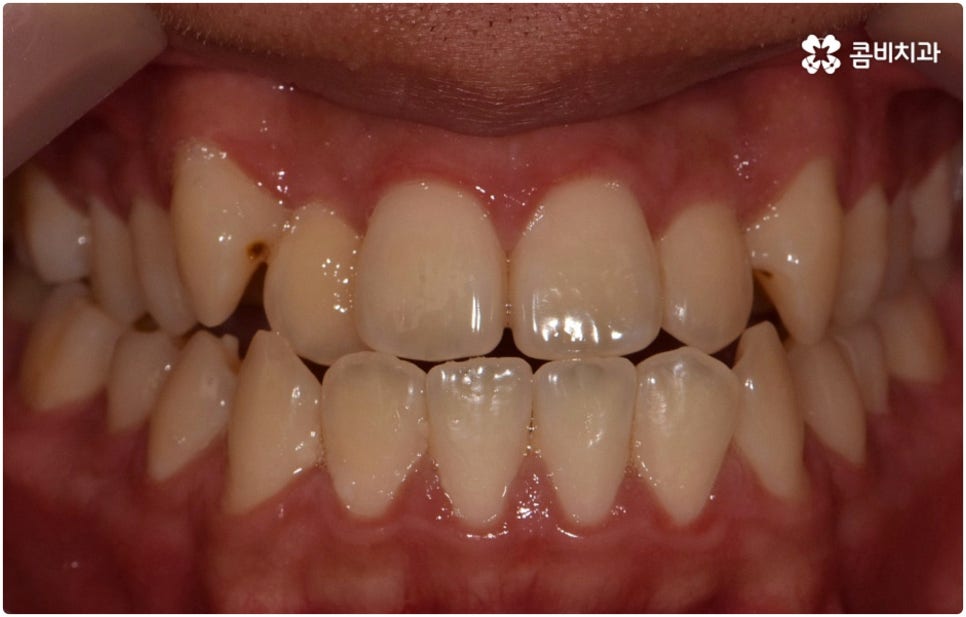

부정교합은 부정교합 1급, 부정교합 2급, 부정교합 3급 이렇게 세가지 종류로 나눌 수 있는데요. 부정교합 1급은 이를 다물었을 때 위아래 어금니는 잘 맞물리지만 덧니가 있거나 치아 사이가 살짝 벌어져 있는 경우처럼 치열이 삐뚤어진 경우를 말하는 것으로 골격이나 구조적인 부분에는 크게 문제가 없기 때문에 정도가 심하지 않다면 보다 빠르고 간편한 교정 치료가 가능한 케이스라고 할 수 있어요. 부정교합 2급은 상악이 하악보다 더 튀어나온 상태로 위에서 언급했던 무턱, 돌출입이 여기에 속하며 반대로 부정교합 3급 은 주걱턱처럼 하악이 상악보다 튀어나온 상태를 의미하고 있습니다.

혹시 부정교합이라는 말을 들어보신 적이 있으신가요? 부정교합이란 쉽게 말해 위아래 치아가 제대로 맞물리지 않는 것을 의미하는데, 보고된 바에 따르면 (연구마다 조금씩 차이가 있지만) 우리 나라 사람 중 적게는 30% 에서 많게는 80%에 달하는 사람들이 이러한 부정교합을 가지고 있다고 알려져 있습니다. 이를 앙 다물었을 때 어금니가 서로 잘 맞물리고 위 앞니가 아래 앞니를 살짝 덮는 정도로 가리는 것을 정상적인 교합이라고 한다면 덧니와 같이 치열 자체가 삐뚤빼뚤한 경우 또는 무턱, 주걱턱처럼 위아래 치아가 긴밀하게 맞물리지 않고 비정상적으로 정렬된 경우를 부정교합이라고 할 수 있는데요. 위에서 언급한 수치로 보건데 생각보다 많은 사람들이 이러한 부정교합으로 인해 불편을 겪고 있는 거예요.